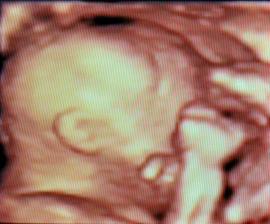

✿♥♥♥♥Bude to dievčatko!!!!! ♥♥♥♥✿

Bude to Stella 🙂

krasne 3D sono 🙂

Krasne foto dufam ze ti uz je lepsie mojko 🙂